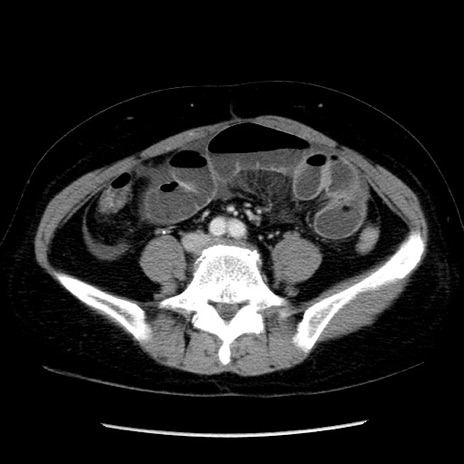

症例6(横断像)

【症例】50歳代女性

【主訴】下腹部痛

【現病歴】本日朝より下痢2回あり。 昼食を食べた後、嘔吐3回、下腹部痛認め、症状軽快せず、当院救急搬送。

【既往歴】卵巣癌術後(8年前に当院で卵巣摘出)

【身体所見】 意識清明、腹部:平坦、腸蠕動音→、やや硬、下腹部自発痛・圧痛あり、反跳痛あり、筋性防御なし。

【データ】WBC 16000、CRP 0.01